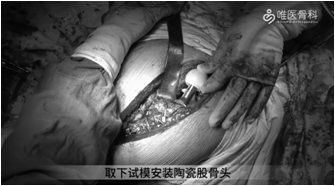

④给予多重钢丝、钛缆捆扎修复截骨块。取下试模,安装陶瓷股骨头,复位后再次检查髋关节稳定性和下肢长度。